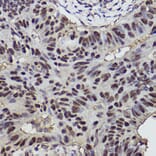

Immunohistochemistry analysis of paraffin-embedded human colon carcinoma tissue using Anti-p53 Antibody (A309435) at a dilution of 1:300 (40x lens). Perform high pressure antigen retrieval with 10 mM citrate buffer pH 6.0 before commencing with IHC staining protocol.